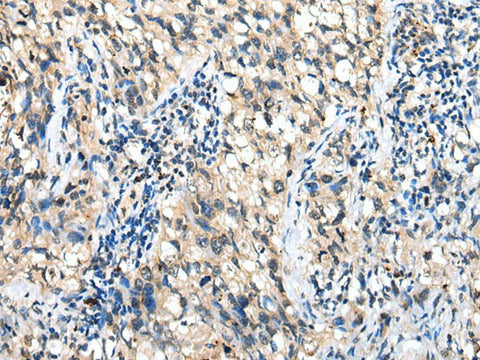

Applications WB, IHC

IHC 1:25-1:100